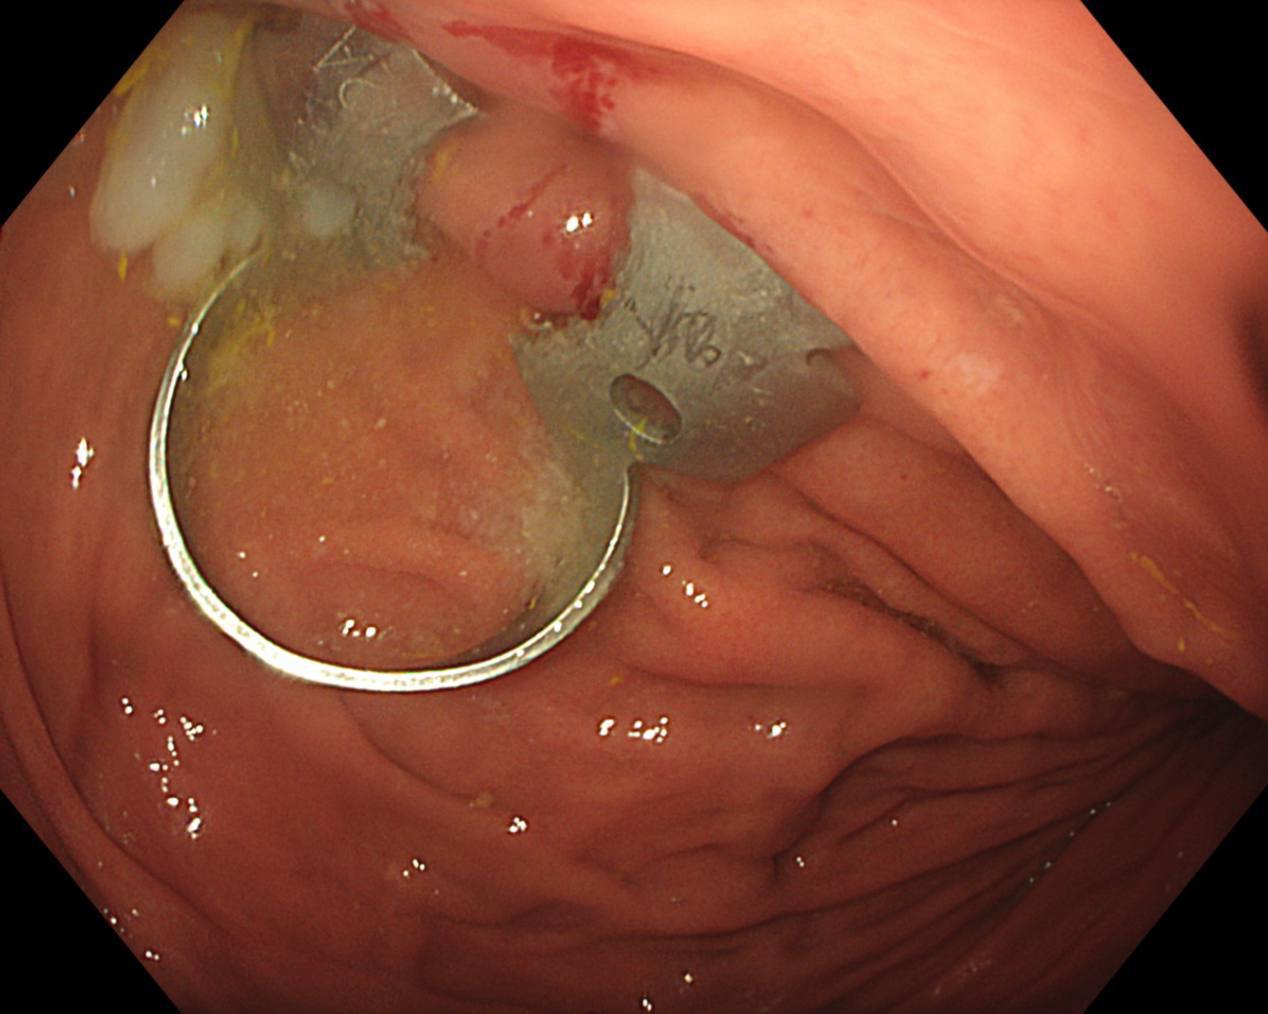

— Для извлечения инородного тела мы выполнили гастроскопию, в ходе которой захватили стоматологическую скобу эндоскопической петлей. Так как инородный предмет был острый, то это создавало высокие риски травмировать слизистую, мы поэтапно провели скобу через пищевод, устье пищевода и гортаноглотку. Процедура длилась около 10 минут и прошла успешно. При контрольном осмотре травматических дефектов слизистой не определялось, — сказала врач-эндоскопист Анастасия Лазарева.

На данный момент с девочкой все хорошо, ее выписали на следующий день после поступления. К счастью, стоматологическая скобка не успела навредить желудку.